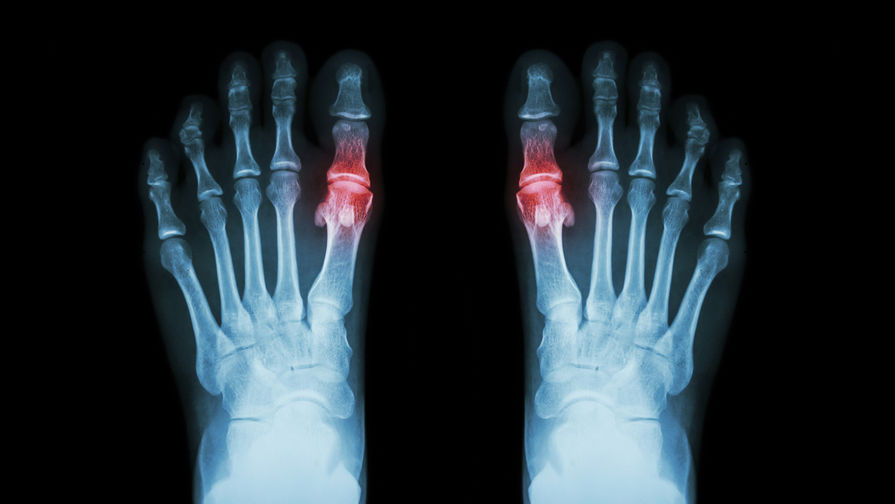

Подагра является наиболее распространенным видом воспалительного артрита, вызванного отложениями в суставах солей мочевой кислоты. Заболевание сопровождается нестерпимой, быстро нарастающей и проходящей за несколько часов или суток болью в суставах, при этом кожа над ними краснеет, а сами они увеличиваются в объеме. Из других симптомов — повышенная температура тела, слабость, потливость. В запущенных случаях на суставах могут образовываться наросты.